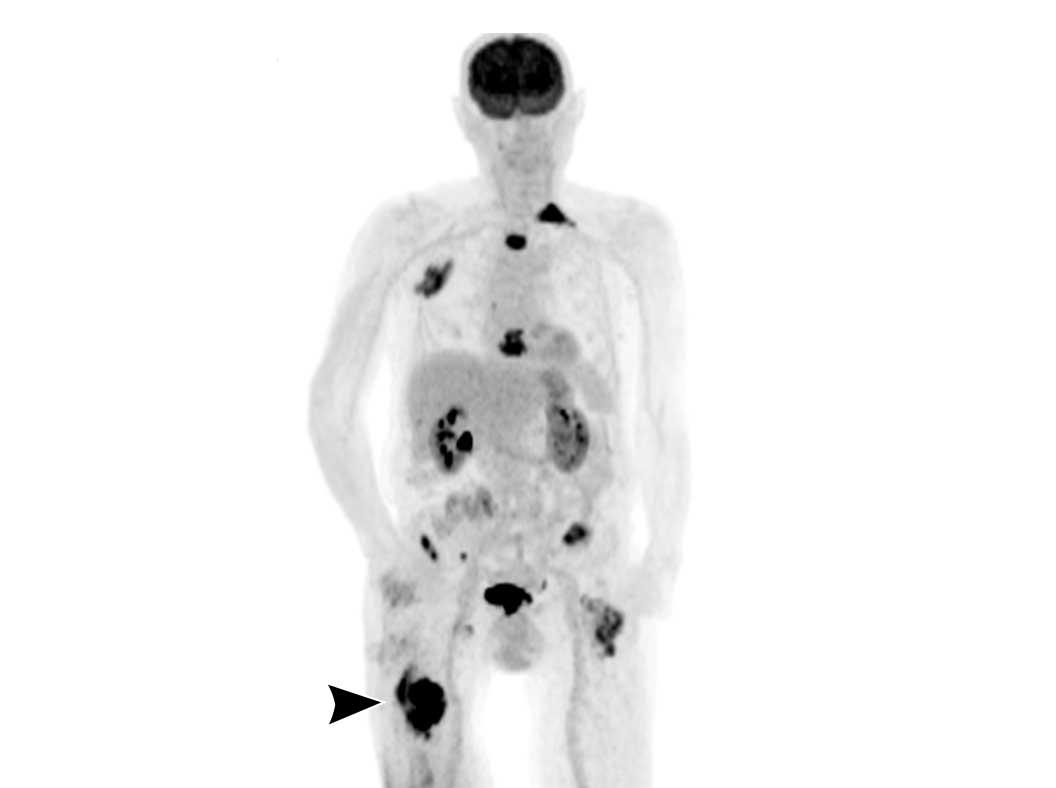

PET-CT

Đối với 18F-FDG-PET-CT, SUVmax đã được chứng minh có tương quan với độ mô học trong các khối u sụn.

SUVmax < 2 ủng hộ chẩn đoán khối u lành tính, trong khi SUVmax > 4,5 gợi ý u sụn ác tính độ cao hơn.

Tuy nhiên, do phần lớn các tổn thương ACT/độ I nằm trong nhóm trung gian với các giá trị chồng lấp (SUVmax 2 – 4,5), PET-CT không được khuyến cáo để phân biệt các khối u sụn.

PET CT toàn thân có thể hữu ích trong việc phát hiện di căn trong ung thư sụn kém biệt hóa.

Hình ảnh

Sarcoma sụn kém biệt hóa ở xương đùi phải (đầu mũi tên) với nhiều di căn.

Continue with the PET-CT…

Chúng tôi đã thảo luận trước đây rằng 18F-FDG PET-CT không được khuyến cáo cho u sụn ác tính để phân biệt giữa khối u sụn không điển hình và các khối u độ cao.

Tuy nhiên, trong ung thư sụn dạng biệt hóa,

PET CT kết hợp với CT chẩn đoán lồng ngực có thể được thực hiện để tìm kiếm bệnh di căn.

Ung thư sụn dạng biệt hóa ở xương đùi phải cho thấy độ bắt giữ FDG cao và hình ảnh toàn thân cho thấy nhiều di căn xương ở xương đùi trái, xương đòn trái, các xương sườn trên bên phải và xương ức.

Di căn hạch bạch huyết cạnh chậu hiện diện ở cả hai bên.

Do chondrosarcoma không nhạy cảm với xạ trị và hóa trị, bệnh nhân được điều trị giảm nhẹ, bao gồm đóng đinh xương đùi phải để phòng ngừa gãy xương.

Thật không may, bệnh nhân đã phát triển gãy xương bệnh lý ở xương đùi trái và sau đó đã được điều trị.

Hình ảnh CT ngực theo mặt phẳng coronal cho thấy khối mô mềm xung quanh

ổ di căn tại xương đòn trái.

Không phát hiện di căn phổi.

Tiên lượng của u sụn dạng biệt hóa kém rất xấu với tỷ lệ sống còn toàn bộ 5 năm khoảng 18%.